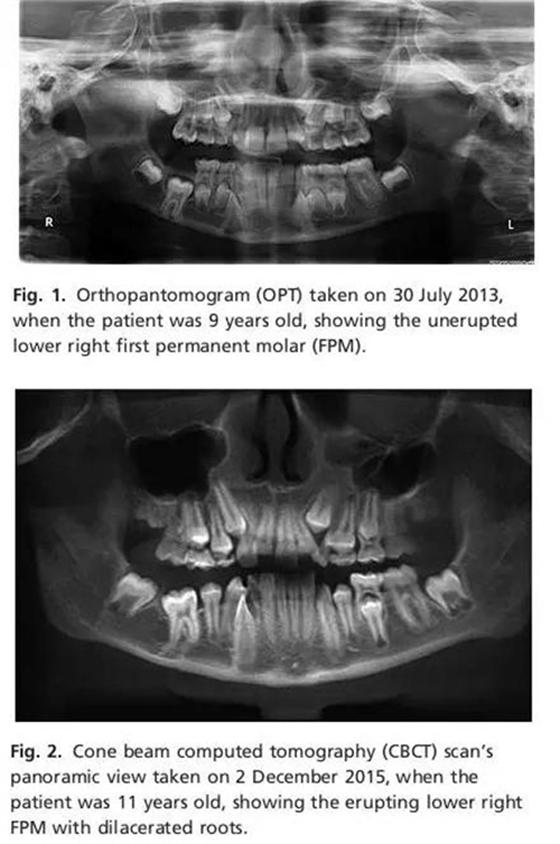

2013年7月13日正畸??漆t(yī)師給患者拍攝全景片。全景片示LR6存在但未萌,根尖接近下頜骨下緣。近遠中根發(fā)育至75%左右,根尖孔未閉合,接近下牙槽神經(jīng)管??梢杂^察到牙囊所在的位置稍微增大但未形成囊腫,牙囊近中位于右下頜第二乳磨牙下方。牙列中其他恒牙萌出正常。

口內(nèi)檢查及影像學(xué)檢查表示LR6萌出失敗,診斷為IFE。要求患者拍攝CBCT以明確LR6牙根與下牙槽神經(jīng)管的位置關(guān)系,考慮是否手術(shù)治療。

患者3個月后復(fù)診拍攝CBCT。臨床檢查發(fā)現(xiàn)LR6近中牙尖開始萌出,遠中牙尖被牙齦覆蓋。影像學(xué)檢查示LR6在牙槽骨中移動,牙根位于LR5和LR7之間?;谝陨蠙z查決定放棄手術(shù)治療,繼續(xù)監(jiān)測患者牙列發(fā)育情況。

本章介紹了11女性患者單側(cè)FPM未萌的病例。LR6是口內(nèi)唯一受累牙,并且可以清楚的看到患牙冠方的萌出通道。CBCT顯示牙根彎曲。這種現(xiàn)象可能與暫時牙槽骨粘連然后萌出有關(guān)。臨床上很少見到FPM患牙5年后恢復(fù)萌出能力,萌出到正常位置。